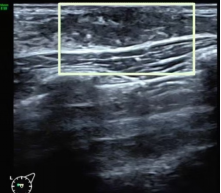

Tanner IV期 纤维腺体组织可清晰显示

(白色方框)